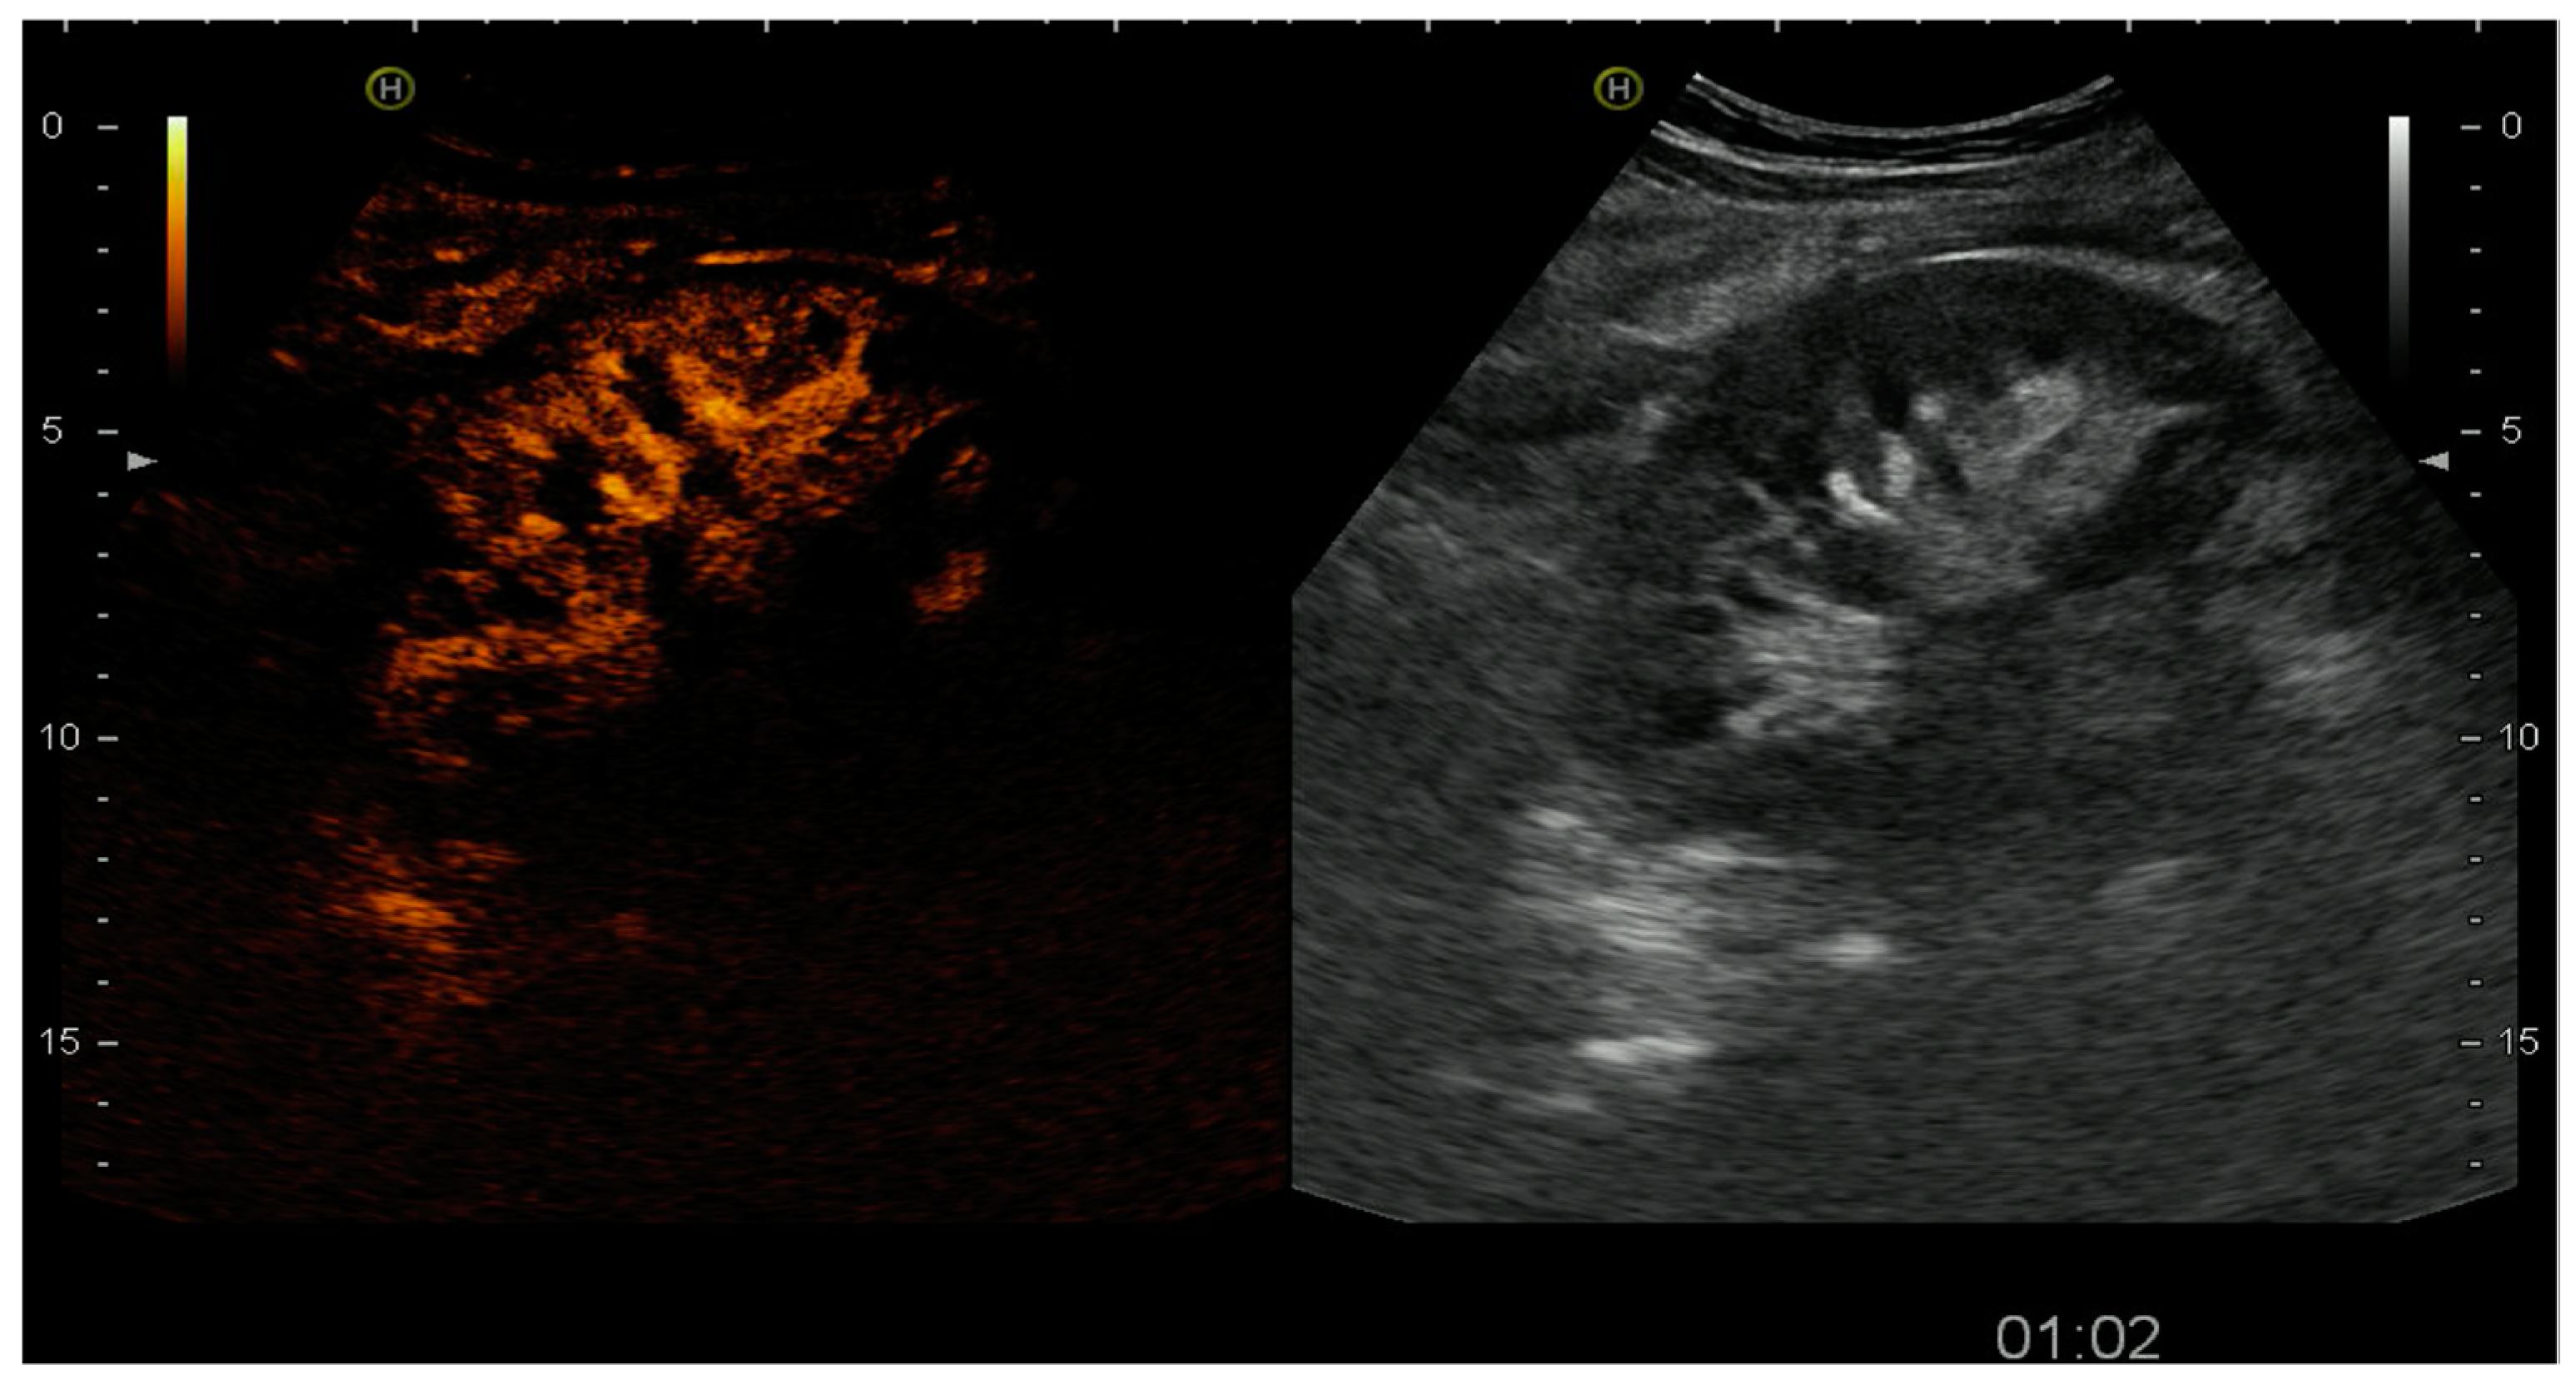

4.1.3. Acute Cortical Necrosis